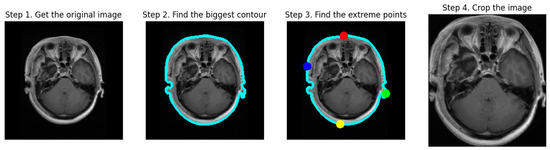

Figure 3 illustrates the process of cropping a brain tumor MRI scan through four distinct steps:

Figure 3.

The cropping process of MRI scans.

- Step 1: Obtain the Original Image. The first image displays the initial MRI scan, capturing the entire head, including the brain and surrounding tissues.

- Step 2: Find the Biggest Contour. In the second image, the largest contour (blue outline) is detected around the brain area, highlighting the primary object of interest.

- Step 3: Find the Extreme Points. The third image indicates the extreme points (red, blue, green, and yellow dots) located on the edges of the brain, which are used for cropping purposes.

- Step 4: Crop the Image. The final image shows a cropped MRI, focusing solely on the brain region and excluding extraneous areas like hair and skin. This step results in a concentrated view of the brain, facilitating subsequent processing and analysis tasks for brain tumor detection and classification.